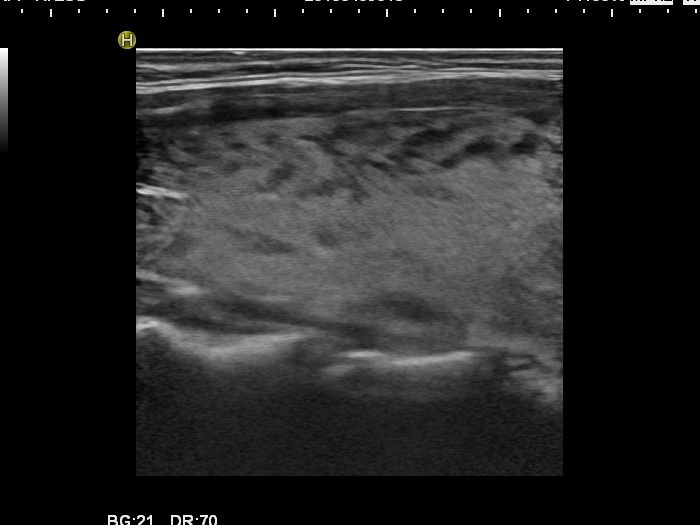

Follow-up investigation 30 months after first visit (ultrasonographic picture 2)

Patient one year after discontinuation of thyrostatics in hyperthyroid state

Right lobe, longitudinal scan.